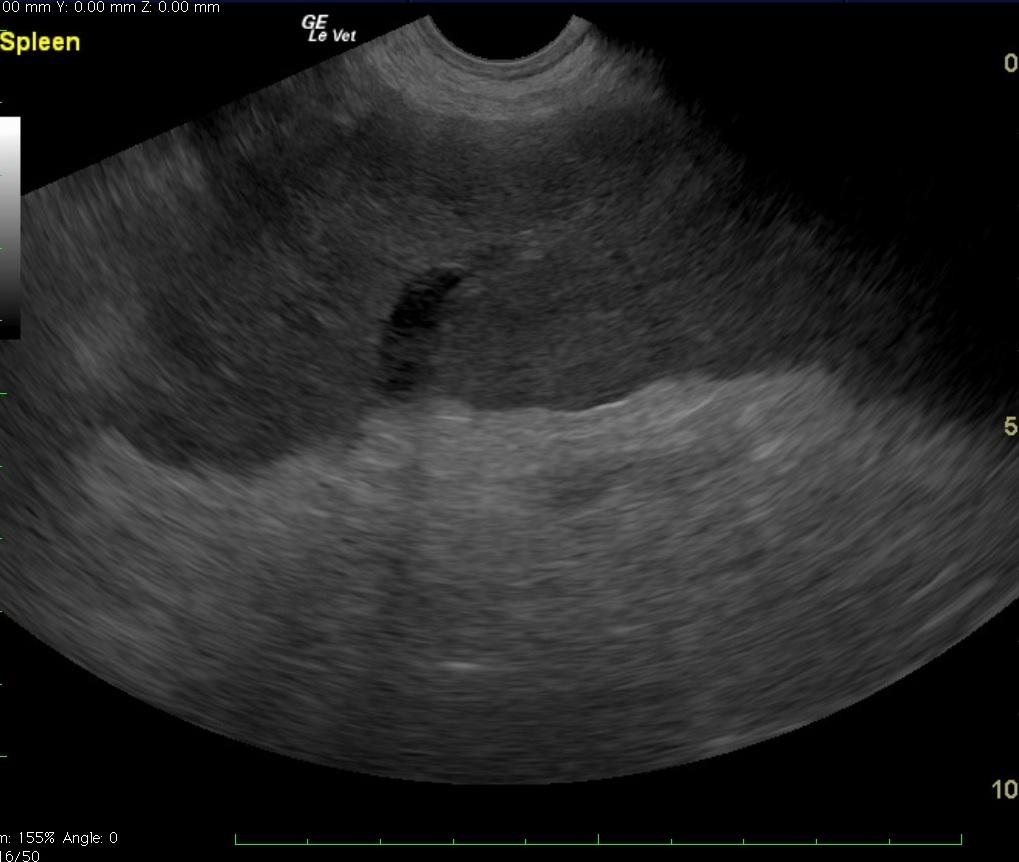

A 6-year-old intact male English Bulldog was presented for 2-3 days of intermittent vomiting and lethargy. Physical exam found the patient to be tachycardic with pale mucous membranes and a palpable mass in the abdomen. Serum biochemistry revealed elevated alkaline phosphatase, hypernatremia, and mild hypochloremia. On CBC, a decreased HCT in conjunction with a high MCV was noted, in addition to a neutrophilia, monocytosis and thrombocytopenia. No abnormalities were noted on thoracic radiographs. Abdominal radiographic findings revealed a loss of contrast in the cranial abdomen, with the possibility of a splenic mass. Radiographic Interpretation showed marked splenomegaly strongly suspected to be secondary to torsion, although accompanying infiltrative or neoplastic pathology could not be ruled out. The small volume of peritoneal effusion and inflammation was likely secondary to the splenic pathology. Thoracic radiographs showed mild microcardia and under perfused pulmonary vasculature in support of hypovolemia. Atypical intrathoracic fat distribution was considered to be incidental in this dog. This dog had multiple hemivertebrae.